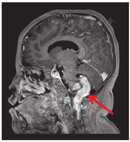

病例2,男,5岁10个月,因"睡眠呼吸暂停2年"于2021年2月25日收入院。入院前2年开始出现睡眠中呼吸暂停,轻度打鼾,于当地医院行腺样体切除术;但术后仍有夜间呼吸暂停,近2个月症状进行性加重,入睡后有明显的口唇发绀,无明显鼾声。近0.5年来有脾气暴躁,无呕吐、头疼、头晕、晕厥等症状。既往史:患儿3岁前生长发育正常,3岁后食欲旺盛,体重及身高增长均快于同龄儿。查体:体型肥胖,身高131 cm,体重55 kg,BMI 32 kg/m2,神志清楚,精神反应好,清醒时呼吸规律,呼吸频率15~25次/min,入睡后呼吸5~10次/min,口唇及甲床发绀,但无明显鼾声,心脏及肺部查体未见明显异常,指鼻试验欠稳准,轮替试验欠灵活,闭目难立征阳性,余神经系统查体未见明显异常。心脏彩超:肺动脉高压(轻-中度)右侧房室饱满。实验室检查:血常规及生化均大致正常。血气分析(静脉血)pH 7.35,CO2分压60 mmHg,氧分压54 mmHg,血氧饱和度86%。PSG相关数据(图5、图6):入睡后无鼾声,OAHI 0.5次/h,CAI 197.4次/h,最低血氧65%,平均经皮二氧化碳分压(transcutaneous partial pressure of carbon dioxide,TCPCO2)82.5 mmHg,快眼球运动期(rapid eye movement,REM)TCPCO2升高明显,平均94.4 mmHg。头颅MRI(图7)示延髓脑干及颈髓背侧占位性病变,病变向后突出推挤四脑室及小脑结构,幕上脑室增宽。诊断为延髓肿瘤、CSA、肥胖症。患儿于外院行肿瘤部分切除术,术后病理为多形性黄色星形细胞瘤。术后患儿偶有夜间呼吸暂停,症状有所改善,仍在长期随访中。

本研究结果发现,56例CSA儿童中,52例(92.9%)CAI在20次/h以下,与气道阻塞存在重叠的病理生理机制。CAI>20次/h有4例,均是出现了中枢神经系统病变,包括Chiari畸形1例,脑干肿瘤2例及遗传代谢病疾病1例。本研究报道的2例病例,均是在完善睡眠监测时,发现呼吸节律异常、间歇低氧、CO2潴留等表现,建议临床完善中枢神经系统查体及影像检查,查找引起CA的原因,最终明确诊断。

呼吸中枢位于延髓,正常情况下延髓呼吸中枢接受化学感受器、大脑皮质的随意控制信号和网状激活系统的行为输入信号,控制呼吸节律。当病变累及延髓时,脑干通气控制中枢功能受损,无法发起呼吸努力,出现CA事件。日间由于皮质信号和行为信号的调控,可以没有明显的呼吸节律问题,在夜间入睡以后呼吸中枢对各种不同刺激的反应性减低,出现低氧,尤其是CO2水平改变引起的呼吸反馈调控不稳定,加重了睡眠呼吸紊乱程度[11]。覃丽霞等[12]对441例1岁以上儿童PSG进行回顾性研究发现,18例(4.1%)儿童的CAI>5次/h,神经外科疾病,特别是Chiari畸形是最常见的CSA原因。检索国内外2000年至2020年报道的延髓脑干肿瘤合并SBD的文献,共8篇,均为个案报道。CSA是延髓脑干肿瘤引起SBD的主要类型[13,14,15,16,17,18,19,20]。CSA相比于OSA,临床症状不显著,患儿多是在夜间入睡后出现异常,容易被忽略,但其实际临床危险度更高[21]。在睡眠监测时发现以CA事件为主时,要密切关注生命体征和CO2变化,病情严重的,随时做好抢救准备。如覃丽霞等[12]报道患者出现睡眠昏迷和呼吸心跳骤停表现,如果不及时发现诊治容易出现猝死。